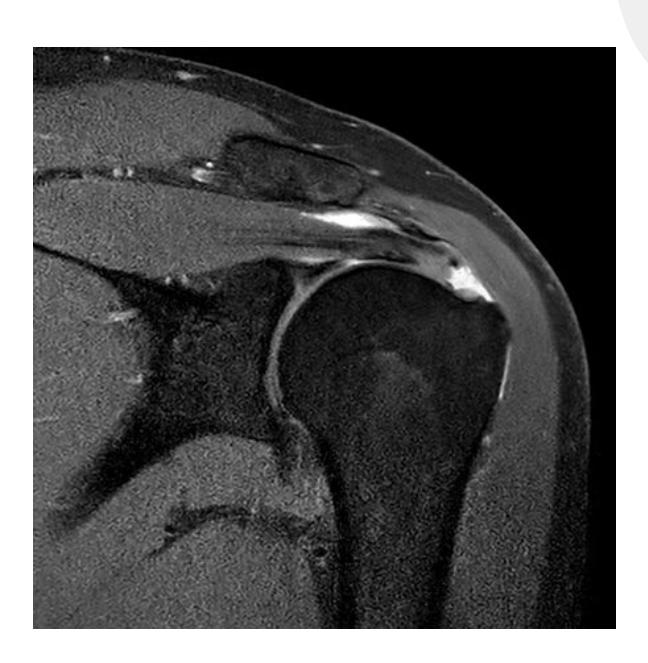

Question 56 - A 45-year-old male with anterior shoulder dislocation. Which injury is demonstrated in the attached MRI?

- d. Supraspinatus tear

Rotator Cuff Pathology

- Common cause of shoulder pain during overhead activities

- May involve tears in subscapularis, infraspinatus, or supraspinatus muscles

- Diagnosis confirmed with MRI imaging

Shoulder Disorders

Question: A case scenario that was suggestive of an anterior shoulder dislocation in a 45-year-old male. Which of the following injuries is demonstrated in the attached MRI?

- Answer: Supraspinatus tear